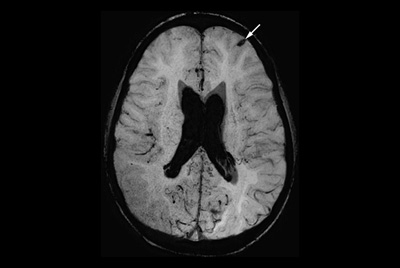

Multiple Sclerosis versus TIA

Brain Multiple Sclerosis

FLAIR* protocol for Multiple Sclerosis